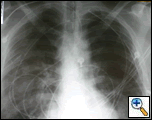

A 44 year old white male with 40 pack-year history of smoking was driving his motor cycle when a car struck him from the left side at approximately 40 mph. The patient lost consciousness at the scene, but upon arrival to trauma bay, he was alert and oriented. He complained of shortness of breath and pain in the left chest and left lower and upper extremity. The trauma team at the referring institution initiated advanced trauma life support pathway. He was found to have left femur, humerus, tibial-fibular and a complex pelvis fractures. The initial chest x-ray revealed a widened mediastinum (Figure 1), and a high-resolution contrast-enhanced computed tomography demonstrated proximal descending aortic rupture with hemomediastinum (Figure 2), left pulmonary contusion and a small left hemopneumothorax.